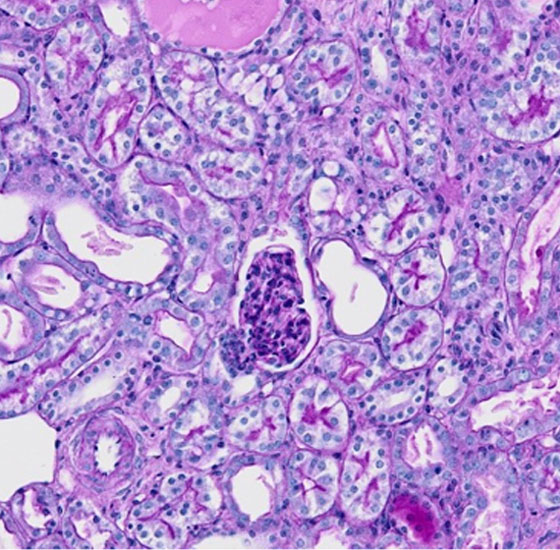

本研究領域では、炎症が収束する際の生体反応を、組織レジリエンス、炎症記憶として研究を進める一方で、慢性炎症時の病態形成機構について、「炎症性組織レジリエンス」、「病的炎症記憶」および「組織障害エントロピー」として捉え、複数の生体システムの連関の観点から研究を推進することにより新たな炎症収束学の創成を目指します。